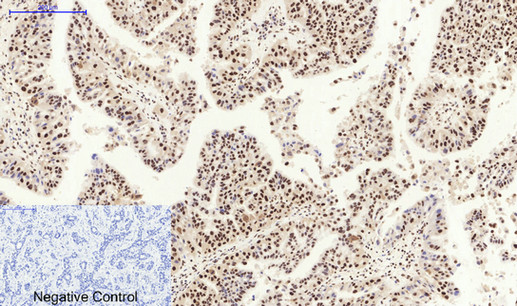

- Scientific DescriptionRabbit polyclonal antibody to MDM2.

- ReactivityHuman